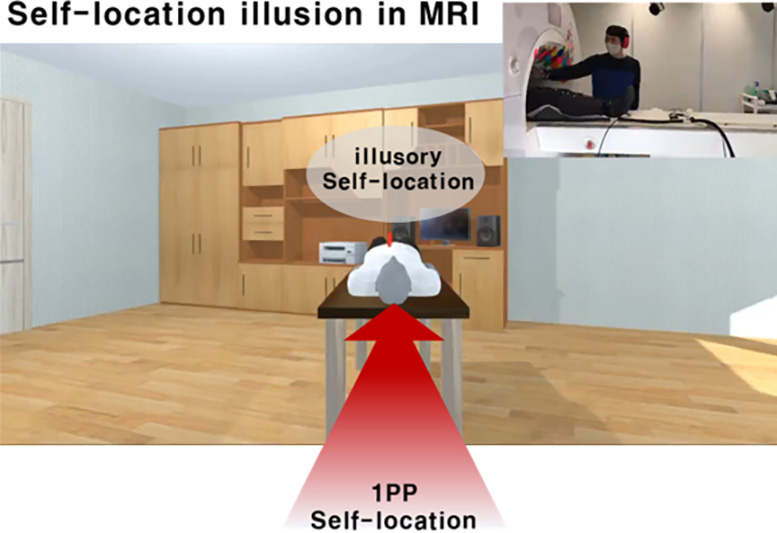

אינדוקציה מבוקרת של אשליית מיקום עצמי באמצעות VR רב חושי בסורק MRI. קרדיט: מכון קוריאה למדע וטכנולוגיה

כדי לצפות בפעילות תאי הרשת במהלך שינויי המיקום העצמי האשלייתיים, שילבו החוקרים טכנולוגיית VR תואמת MRI עם גירוי גוף רב חושי כדי לגרום לאשליה, שנשלטה במדויק בכיוונים שונים כפי שתוכננה. ה fMRI תמונות שנמדדו במהלך הניסוי שימשו להערכת הפעילות של תאי רשת, והחוויות האשליות הסובייקטיביות של המשתתפים הוערכו באמצעות שאלונים לאחר הניסוי ומדדים התנהגותיים המשקפים את מיקומם העצמי הנתפס.